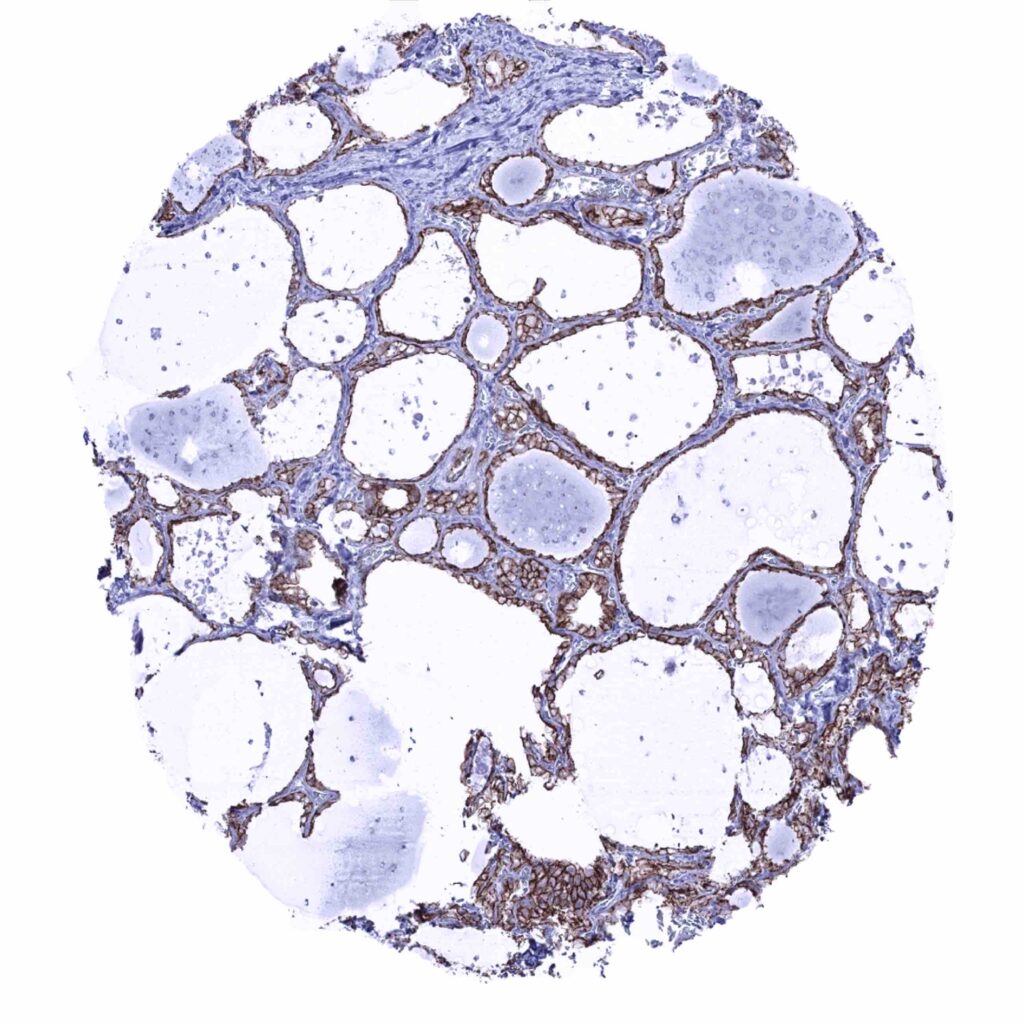

Thyroid gland – Intense membranous occludin immunostaining of follicular cells (occludin immunohistochemistry)